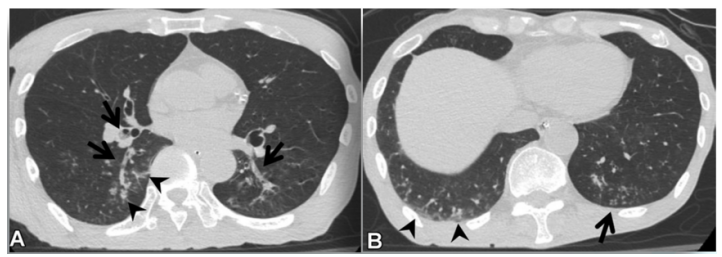

患者于2022年11月10日在全身麻醉下行左肺下叶部分切除+淋巴结活检术,手术过程顺利,入量1200 ml,尿量600 ml,出血10 ml。术后病理提示微浸润腺癌。术后顺利拔除气管插管,生命体征平稳。术后第3天开始出现活动后稍气喘,无明显发热,偶有咳嗽,咳白色黏痰。胸闷气喘症状逐渐加重。肝肾功能正常,D-二聚体正常,心肌标志物正常,未查血气和胸部CT;白细胞、CRP升高明显(表1)。予哌拉西林他唑巴坦+莫西沙星加强抗感染治疗。术后第5天胸部CT可见少量病灶(图2)。术后第12天胸部CT提示两肺间质性改变,右肺为著,局部可见支气管牵拉变形,磨玻璃影(图3)【普通感染不应出现如此变化,但当时并未引起重视】。后续患者出现呼吸衰竭,血气分析:pH 7.34,PaO2 53.1 mmHg,PaCO2 35.1 mmHg(面罩吸氧10 L/min)。转至ICU进一步治疗。

(1)感染性疾病:病毒性?细菌性?真菌?非典型病原体?吸入性肺炎?(2)非感染性疾病:心衰?急性肺栓塞?自身免疫性疾病?麻醉/手术相关肺损伤?急性间质性肺炎?回顾分析患者入院时胸部CT: 双肺靠近外周近胸膜处有轻微细小间质样改变(图4)。诊断:急性间质性肺炎;Ⅰ型呼吸衰竭;左肺下叶部分切除术后;高血压病。ECMO支持;呼吸机支持;甲泼尼松80 mg q12h,尼达尼布;镇静镇痛;抗感染;营养支持。ECMO第6天, 术后第18天, 肺部病变进一步加重(图5)。血气分析: pH 7.543, PaO2 154 mmHg, PaCO2 33.2 mmHg(ECMO, FiO2 100%, MV FiO2 60%)。术后第26天复查胸部CT未见改善。患者最终死亡。笔者团队也曾接诊过一例早期肺癌患者,2013年和2014年随访肺部结节均无明显变化。2015年胸部手术后2天,两肺变白(图6)。当时医生警惕性非常高,立刻行胸部CT检查并予相应治疗,患者最终存活。2022年RadioGraphics 杂志报道一例85岁女性腺癌患者奥希替尼治疗5个月后。图7-A和B为治疗前胸部CT图像,可见右肺中叶有肿块(A中箭头)。胸膜下区域磨玻璃改变和网状结构(箭头)提示存在间质性肺异常(Interstitial Lung Abnormalities,ILA)。治疗5个月后的轴位CT图像显示肿块(C中白色箭头)、弥漫性磨玻璃改变和合并症(黑色箭头)。图源:Radiographics, 2022, 42(7):1925-1939.另一例66岁右上肺鳞癌患者,术前CT显示肿块(图8-A中箭头)位于肺右上叶。轻度磨玻璃改变(箭头),提示ILA,见于胸膜下区域。图8-C和D为术后CT,显示弥漫性磨玻璃样改变和实变(箭头),牵引性支气管扩张症(图8-C中箭头),也可见胸腔积液(图8-D中箭头)。图源:Radiographics, 2022, 42(7):1925-1939.